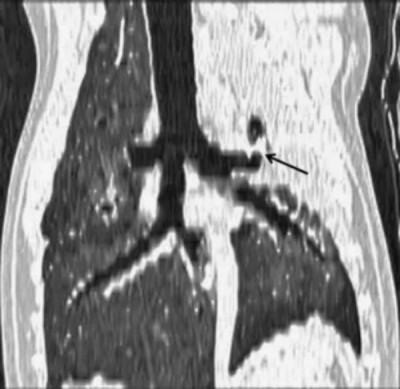

图2. 一只8岁阿富汗猎犬左前叶肺扭转的胸部背侧重建计算机断层扫描(CT)图像。通向左前叶的支气管突然中断(箭头),而更远端的节段再次充满气体并扩张,使支气管呈现扭曲的外观。